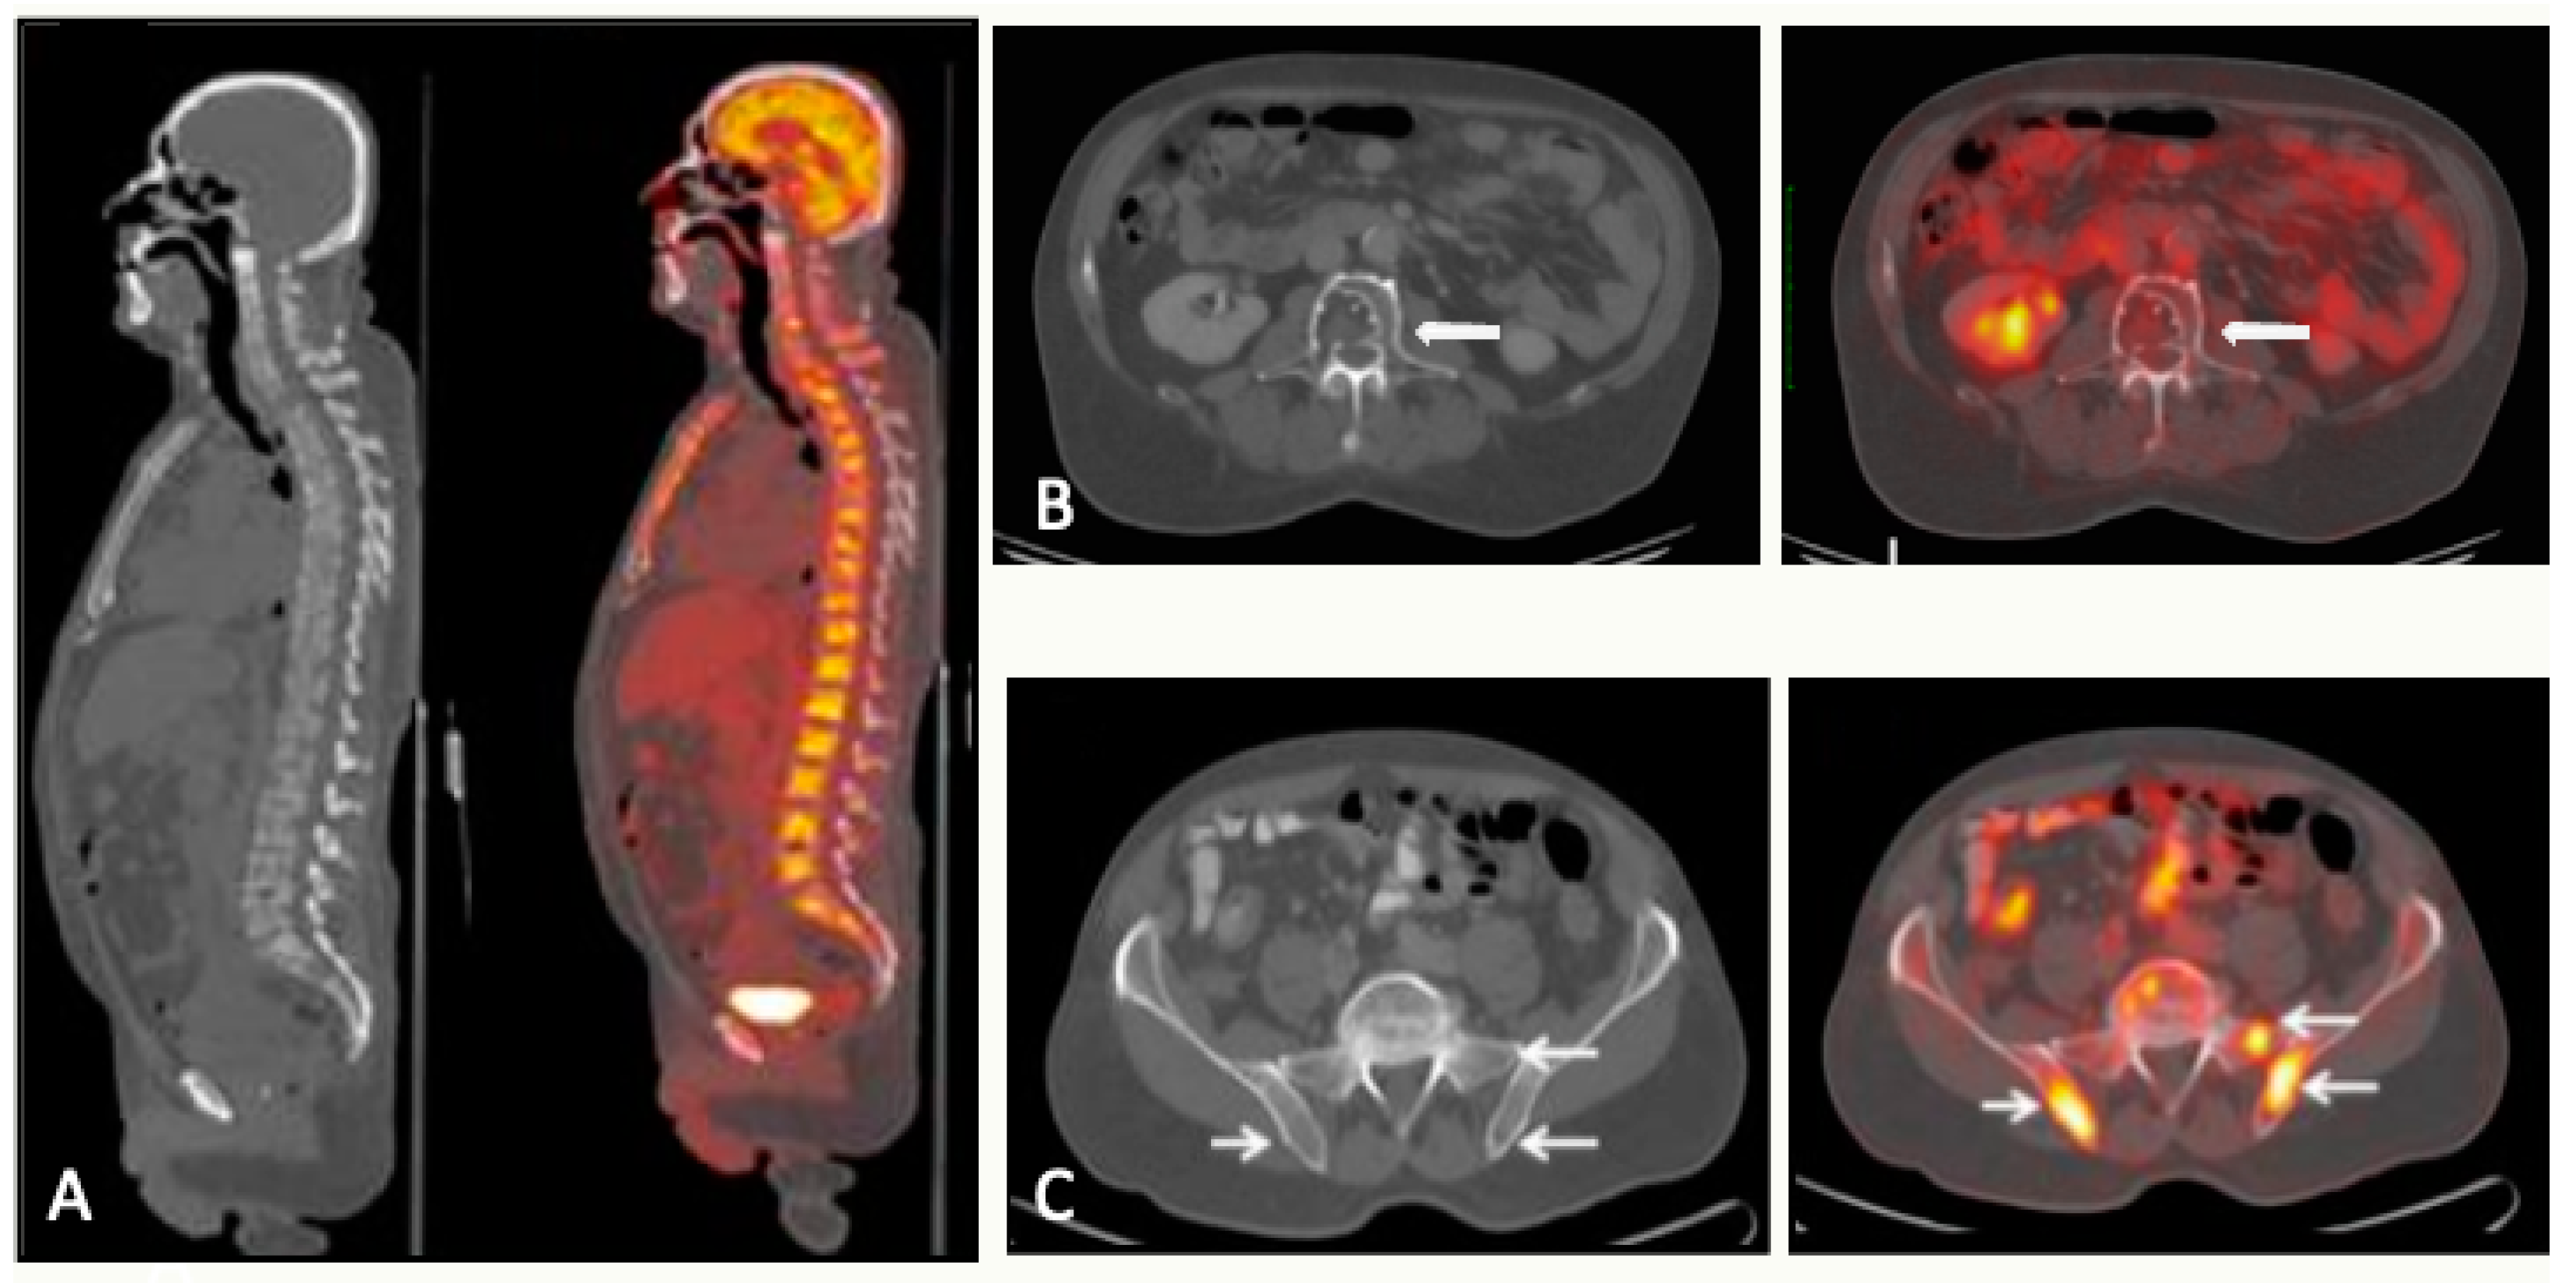

5. PET

5.1. PET/CT

5.1.1. Technique and Image Analysis

5.1.5. FDG-PET/CT vs. WBMRI

5.2. FDG-PET/MRI

5.3. Summary